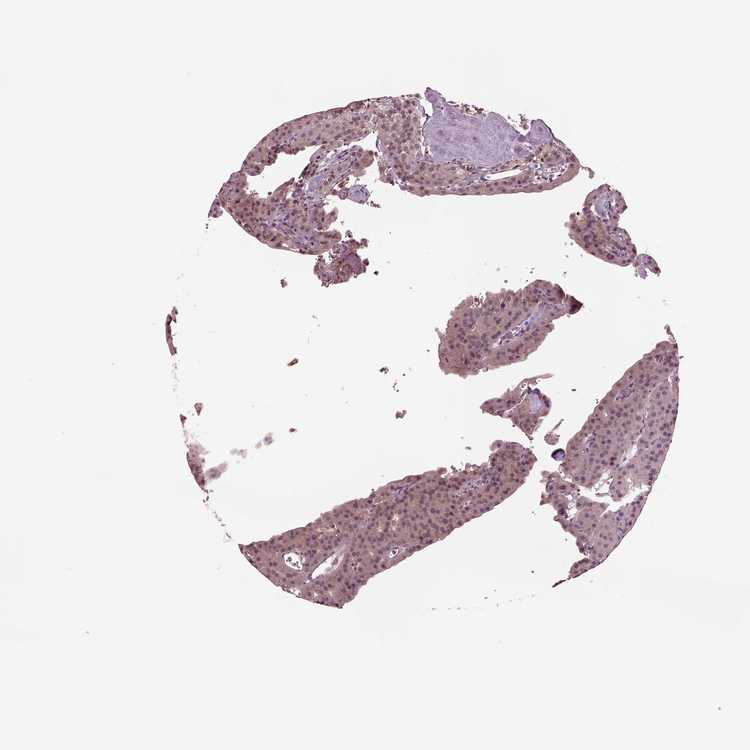

TISSUE PRIMARY DATA PARATHYROID GLAND Show tissue menu

PARATHYROID GLAND - Antibody stainingi

Antibody staining in the annotated cell types in the current human tissue is reported as not detected, low, medium, or high, based on conventional immunohistochemistry profiling in selected tissues. This score is based on the combination of the staining intensity and fraction of stained cells.

Each image is clickable and will lead to virtual microscopy that enables deeper exploration of all samples and also displays staining intensity scores, fraction scores and subcellular localization as well as patient and tissue information for each sample.

Antibody HPA019004Antibody HPA073666

Glandular cells Not detectedNot detected